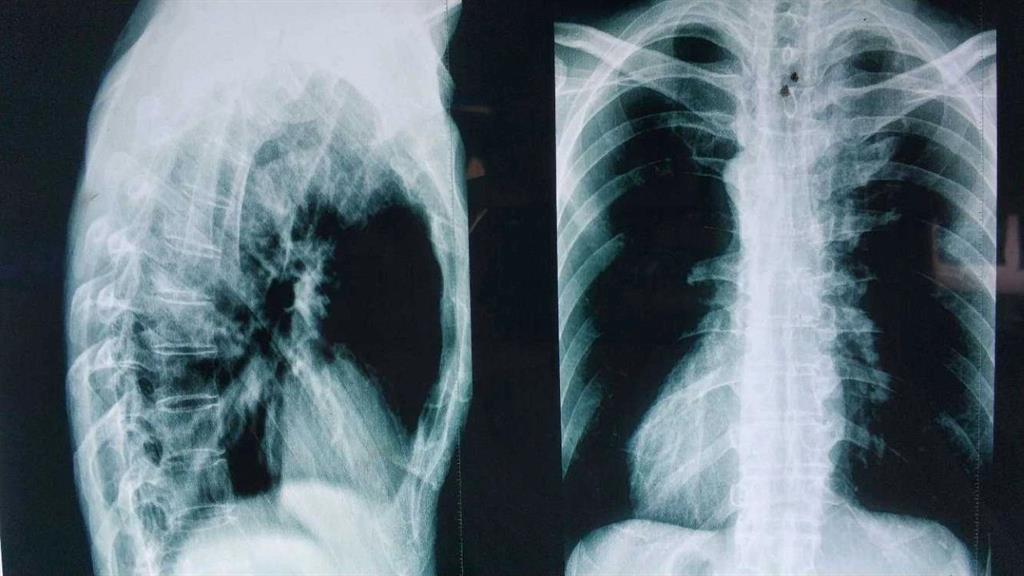

“HLA-B27陰性……從驗血報告來看是正常的……X光……也沒什么問題,這邊建議你再去拍個髖關節的核磁共振。”醫生轉過身對著男孩說。

“這是之前拍的磁共振的片子。”

醫生接過片子對著燈源看了看。

“這片子拍的不行,你要照我說的部位拍。”

“你這病本來就應該到風濕免疫科來看,你之前去的骨科診斷會不一樣,現在這個片子看不到病痛的地方。”

“大醫院都這樣,病人多拍片排隊的隊伍長,你可以去其他醫院拍拍好后有片子就行。”

“小伙子!因為你說拍片是為了確實是否為強直性脊柱炎,我們剛才在拍片的時候發現按照那邊醫生要求的部位拍攝還是看不到病癥點,所以我們給你拍了兩次,你到時候給醫生看的時候都給他看。”